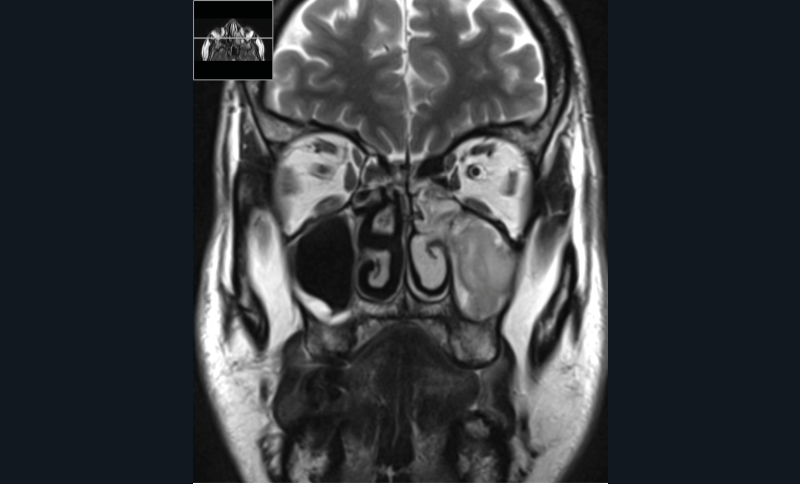

La tomodensitométrie des sinus retrouve un comblement complet unilatéral du sinus maxillaire gauche et des cellules ethmoïdales antérieures homolatérales, sans image de densité calcique intrasinusienne et sans lyse osseuse des parois (fig. 1). L’IRM montre un épaississement tissulaire de 23 mm de grand axe en regard du méat moyen gauche, avec un aspect de signal T2 hétérogène (fig. 2) et prenant le contraste en masse (fig. 3). Le comblement maxillaire gauche associé à un épaississement muqueux en cadre rehaussé correspond à une rétention en hypersignal en diffusion (fig. 4), avec diminution du coefficient apparent de diffusion (moyenne à 433 mm2/s) en faveur d’une pyocèle (fig. 5).